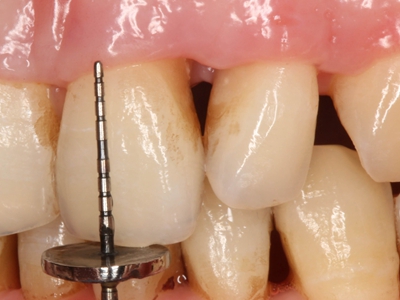

牙龈退缩露出淡黄色牙根图

牙龈退缩患者的牙龈退缩后,淡黄色牙龈明显露出。若进一步发展,易使对应位点的牙槽骨发生骨吸收,可能诱发龋齿、牙龈敏感、菌斑堆积等。